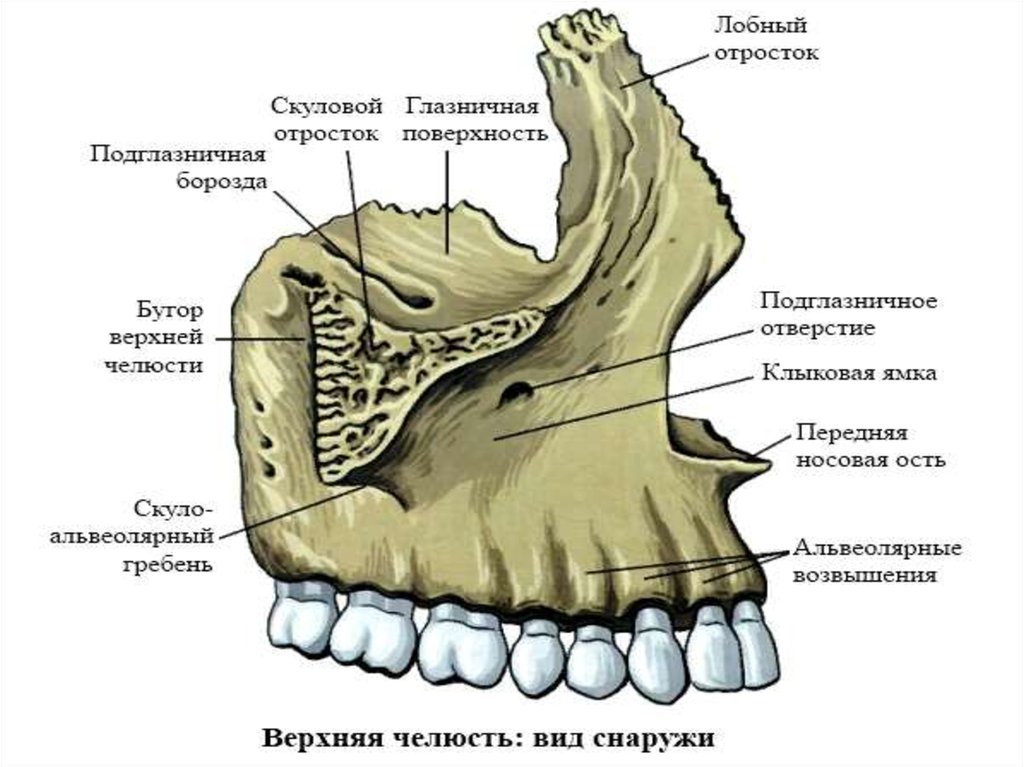

Анатомические изображения срединной сагиттальной линии черепа